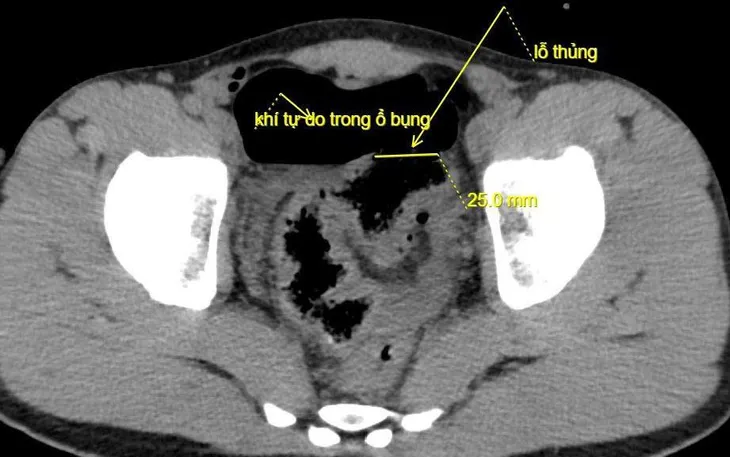

Kết quả chụp CT ổ bụng cho thấy nhiều khí tự do trong ổ bụng, nghi ngờ thủng tạng rỗng. Bệnh nhân được chỉ định mổ cấp cứu ngay. Trong quá trình phẫu thuật, ekip phát hiện đại tràng sigma thủng 2cm, dập nát quanh vùng tổn thương, có máu và dịch bẩn trong ổ bụng. Các bác sĩ đã tiến hành cắt lọc, khâu phục hồi đại tràng, rửa ổ bụng và dẫn lưu. Hiện bệnh nhân tỉnh, bụng mềm, trung tiện được, sức khỏe ổn định.